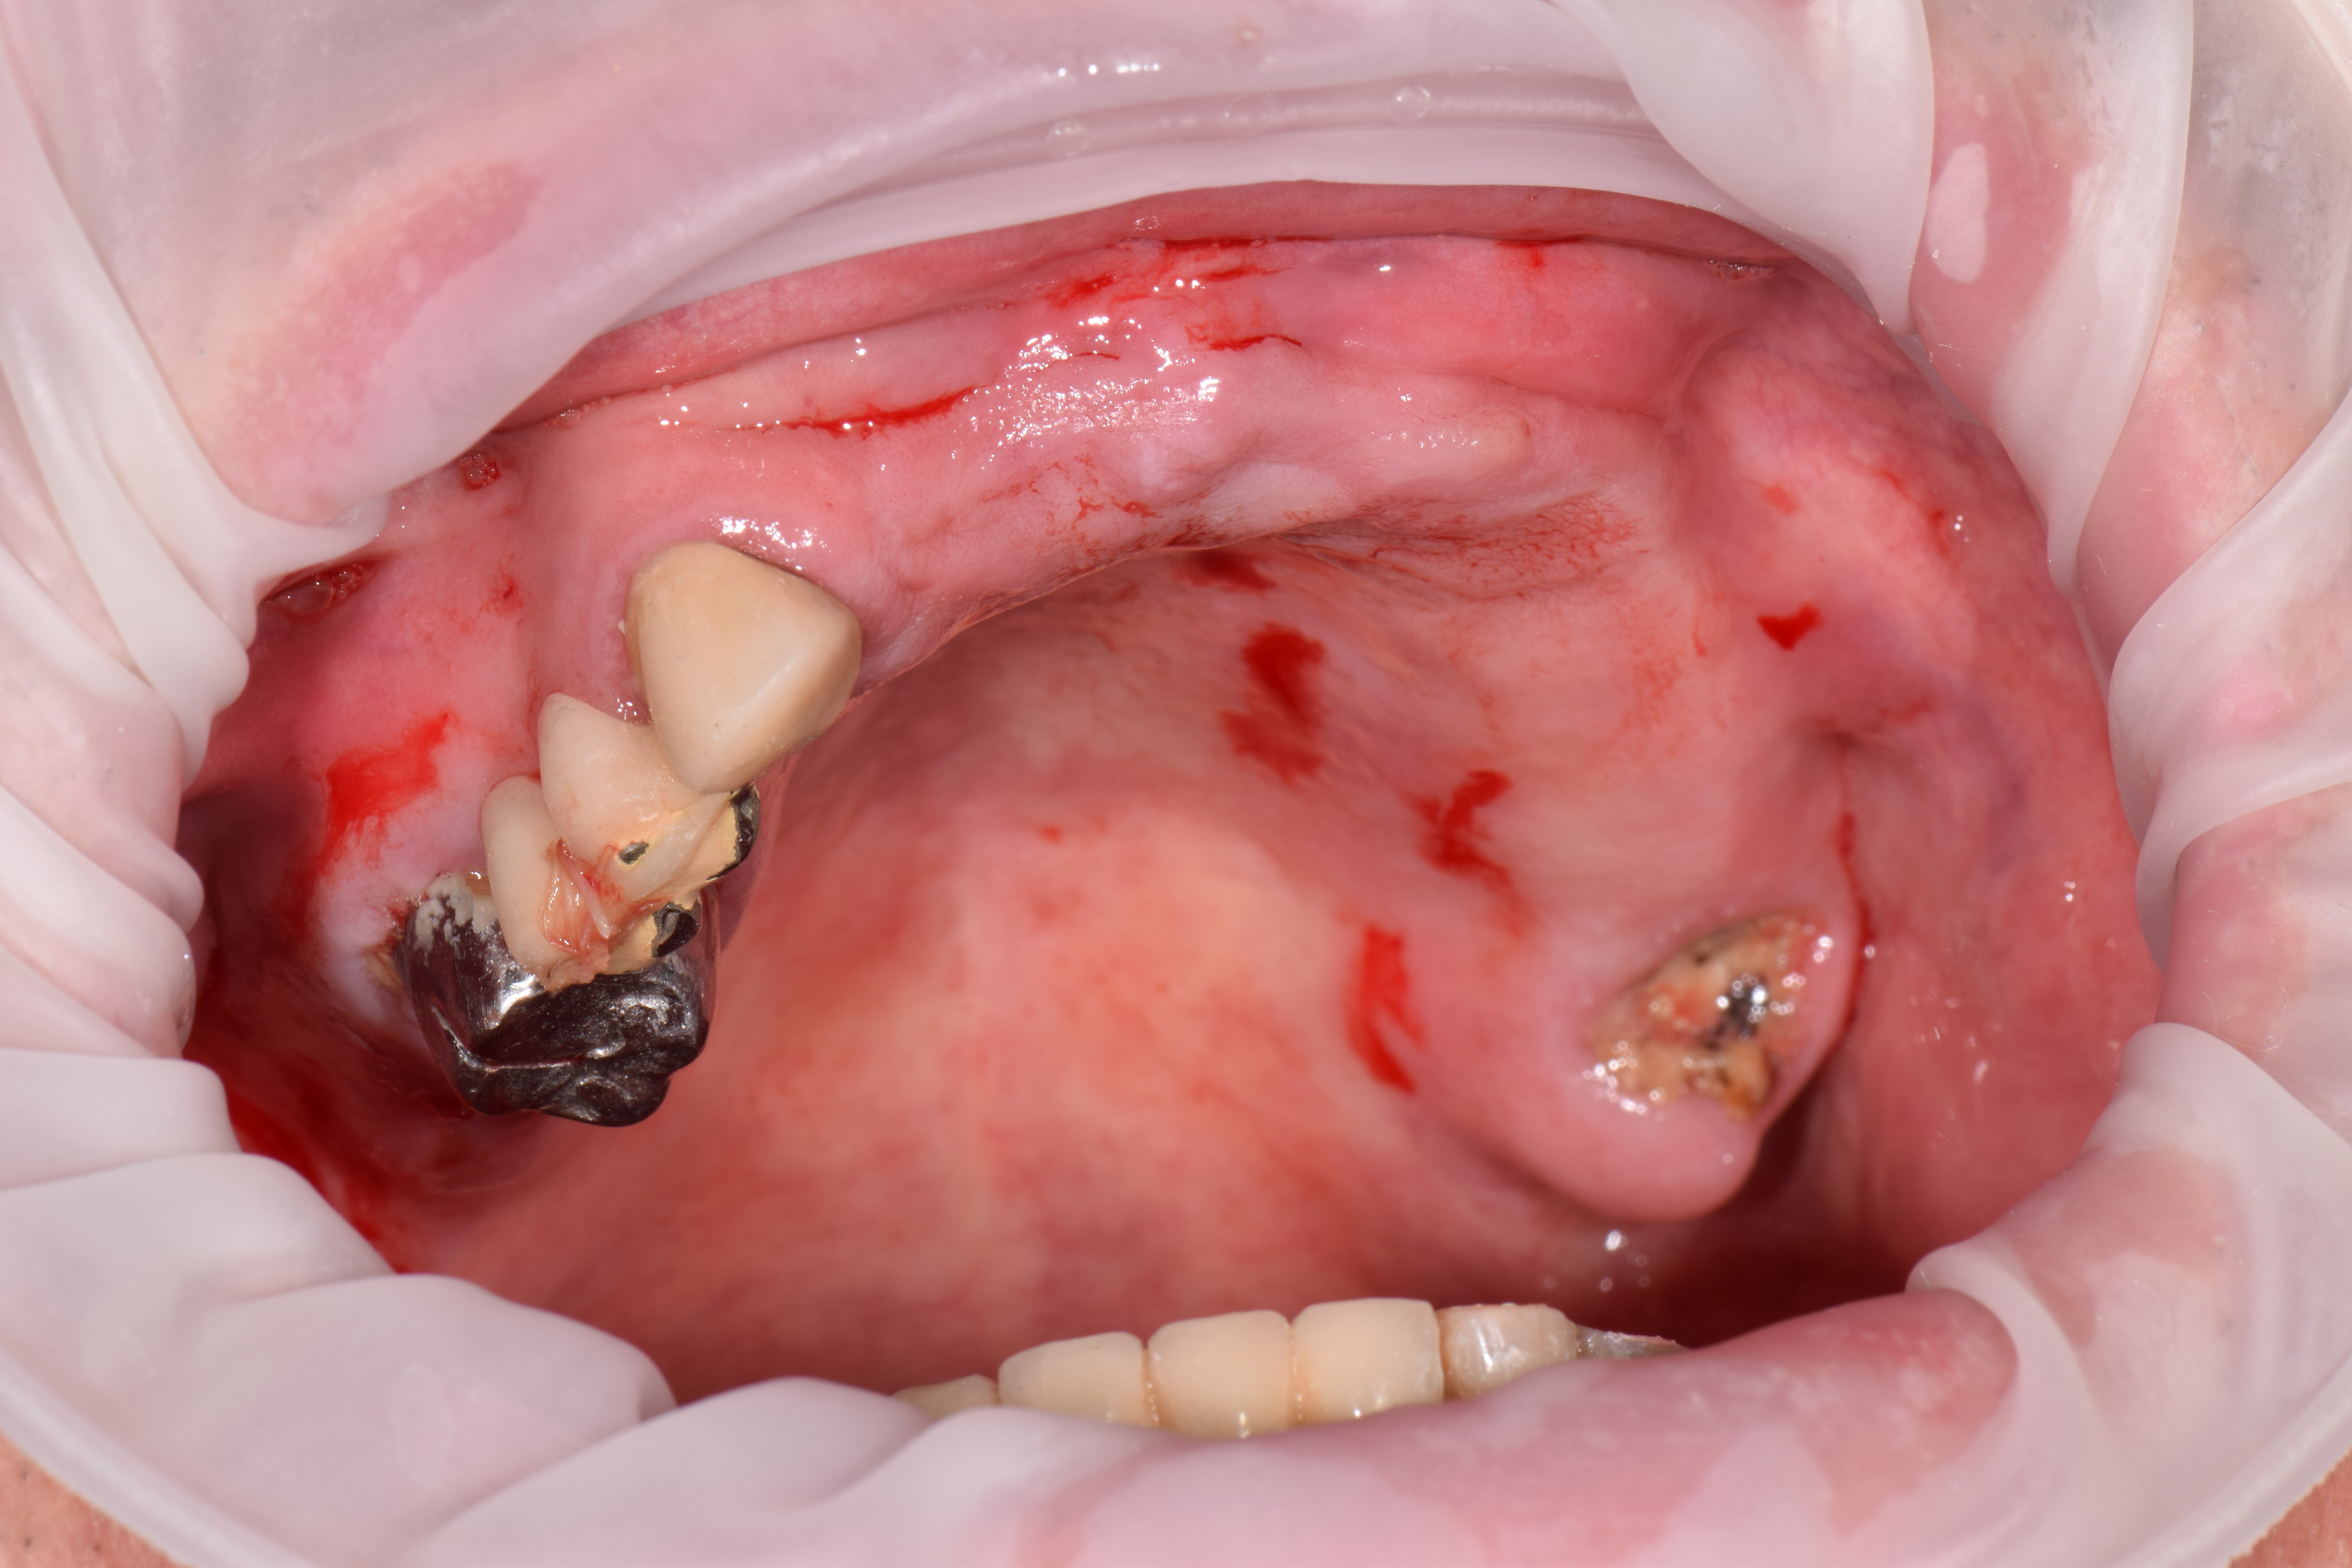

| УДАЛЕНИЕ |

|

|